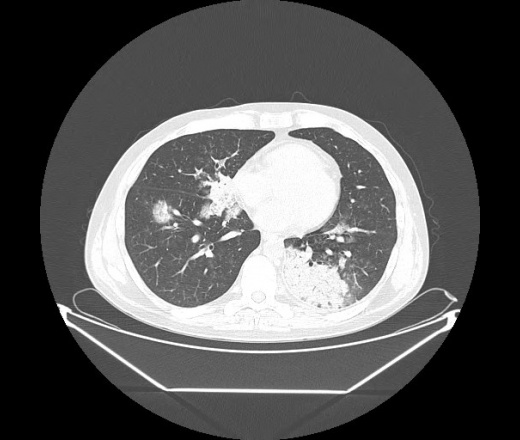

М. 1984 г.р.  Лихорадка 39, кашель , одышка.. и надоевший всем вопрос- "типично ли для ковид?" ( в настоящее время на него обязательно нужно дать ответ в своем протоколе)

На мой взгляд нетипично для ковид: много центрально-расположенных поражений, лобарное поражение нижней доли слева. 50/50

Не типичая картина для ковид.

КТ-признаки двусторонней бактериальной пневмонии.

Все верно, здесь абсолютно нетипичная картина, несмотря на матовое стекло с ретикулярными изменениями, но почему-то  посчитали иначе. Кстати,  "малыша" не заметили)?

Добавил 6 день

Что за малыш? Будущий абсцесс? Не заметил. Только о туберкулёзе подумал

+ 1?  Зона очень похожа была на формирующийся абсцесс, даже по рентгенпризнакам. Еще хотела спросить, но постеснялась. А на контроле видно

да, это я о абсцессе.